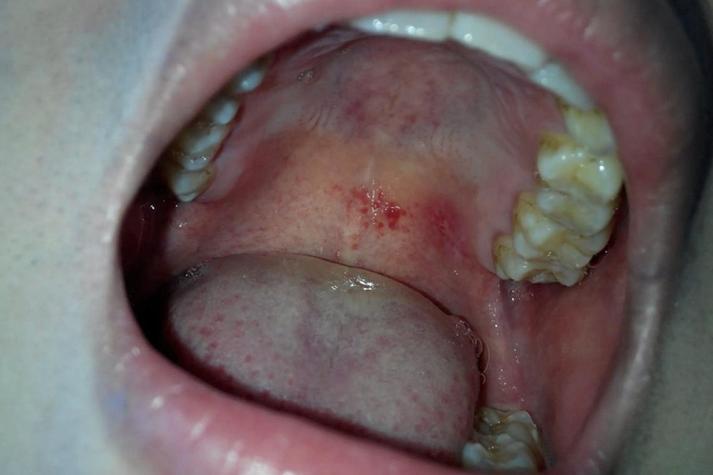

病毒感染

(图片来源网络,侵删)- 疱疹性口炎:由单纯疱疹病毒引起,初期可能在口腔任何部位(包括上颚)出现成簇的小水疱,很快会破溃形成小溃疡,伴有疼痛、灼热感和发热。